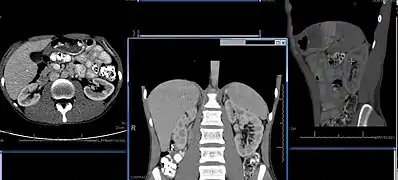

Chronic kidney disease (CKD) has been recognized as a leading public health problem worldwide. The global estimated prevalence of CKD is 13.4%, and patients with kidney failure needing renal replacement therapy are estimated between 5 and 7 million.[6] Procedures used in the management of kidney disease include chemical and microscopic examination of the urine (urinalysis), measurement of kidney function by calculating the estimated glomerular filtration rate (eGFR) using the serum creatinine; and kidney biopsy and CT scan to evaluate for abnormal anatomy. Dialysis and kidney transplantation are used to treat kidney failure; one (or both sequentially) of these are almost always used when renal function drops below 15%. Nephrectomy is frequently used to cure renal cell carcinoma.

Imaging

Renal ultrasonography is essential in the diagnosis and management of kidney-related diseases.[44] Other modalities, such as CT and MRI, should always be considered as supplementary imaging modalities in the assessment of renal disease.[44]